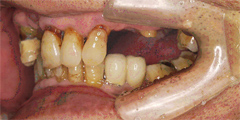

吉本歯科医院においては、口内写真とパノラマレントゲンを撮影し、まずは顎の骨の状態まで詳しく確認しました。

噛み合わせが非常に悪く、上の歯が下の歯にすっぽりと覆いかぶさっておりまともに噛めていない状態であることがわかりました。